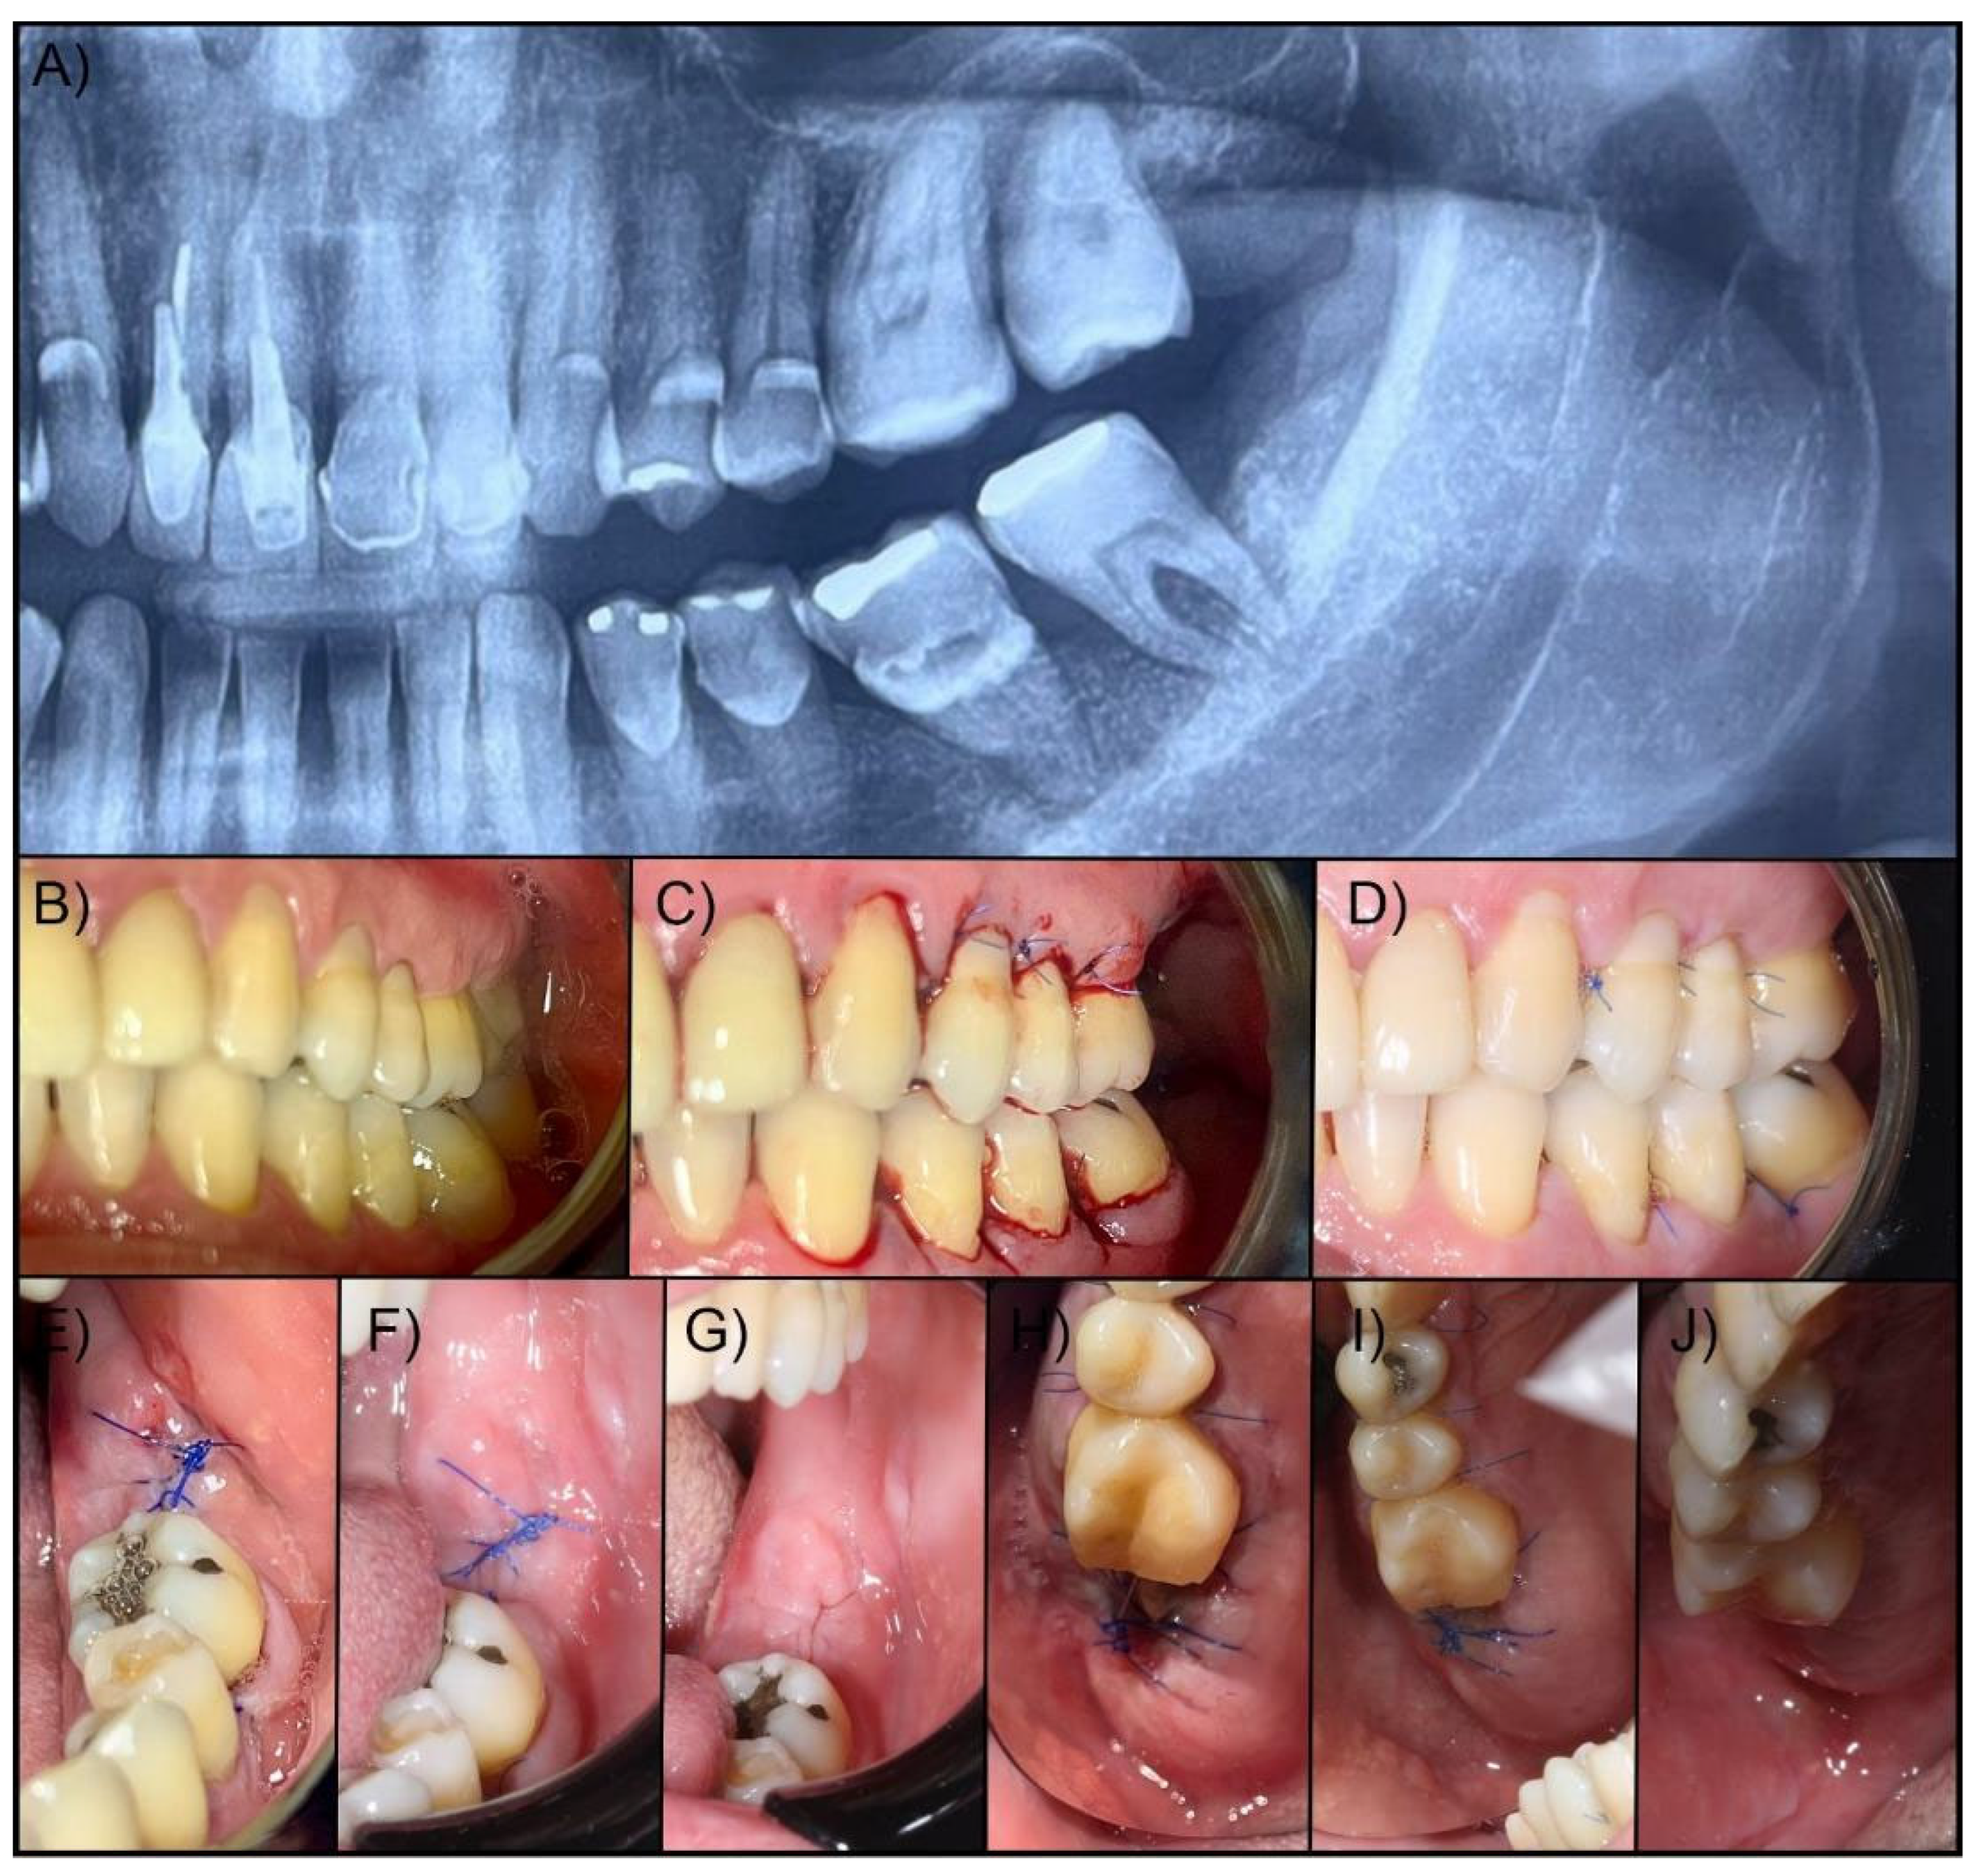

After 30 minutes, 24 and 48 hours, and 7 days after extraction, a control was performed to measure the clinical aspects, hemostasis, pain control, and the amount of analgesic medication required in the postoperative period. The step-by-step surgical procedure and follow-up are illustrated in Figure 1.

Figure 1. Surgical procedure performed on patients in the Lumina Coat® and Hemospon® groups. Patient 1. (A) Preoperative X-ray; (B) Preoperative view; (C) View 30 minutes after extraction; (D) View 7 days after extraction. Patient 2. (E) The immediate postoperative period after extraction of the second lower molar; (F) 7-day postoperative control; (G) Surgical appearance after 7 days. Patient 3. (H) The immediate postoperative period after extraction of the second upper molar; (I) 7-day post-operative control; (J) Surgical appearance after 7 days.